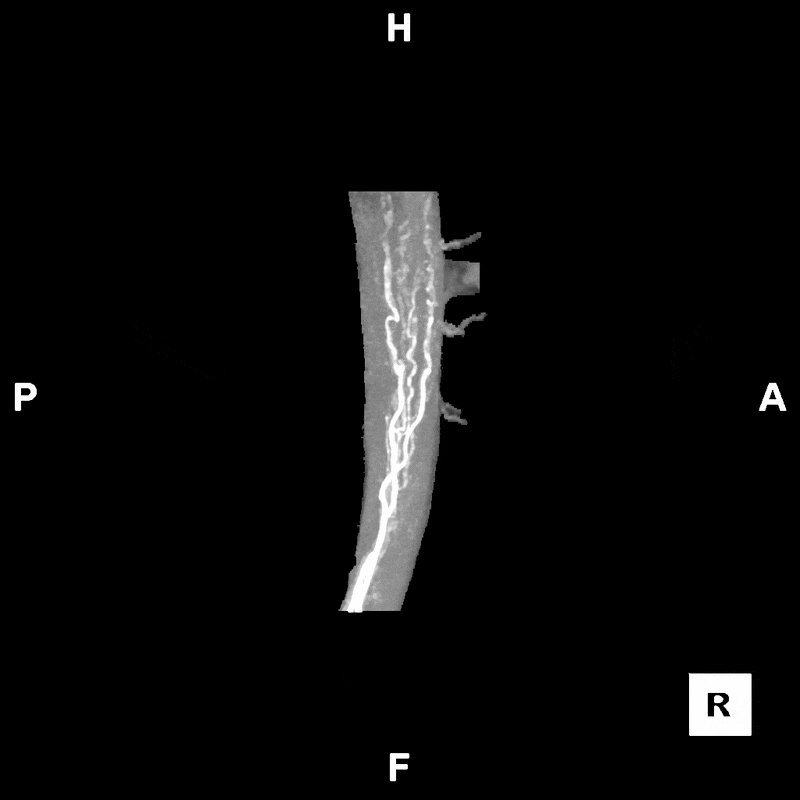

Figure C: Rotating segmented MIP image of the abdomen, provided to clinicians for preoperative evaluation and planning.

3D imaging can play an important role in supporting DIEP flap breast reconstruction by helping surgeons visualize critical anatomy before the procedure. A CT angiogram of the abdomen is performed to capture detailed images of the abdominal wall, with intravenous contrast used to highlight blood vessels. From this scan, radiologic technologists segment the deep inferior epigastric arteries and their perforating branches which supply blood to the flap tissue (these vessels exit the abdominal wall and reach into the belly fat). The umbilicus is segmented as a landmark, and the rectus abdominis muscle (ab muscle) is included to show the course of the vessels through the muscle layer. This mapping allows surgeons to identify the most favorable perforators and understand their spatial relationships, which vary from patient to patient. The segmented data is then sent to clinicians through the hospital’s PACS system, providing a digital reference for preoperative review and planning.